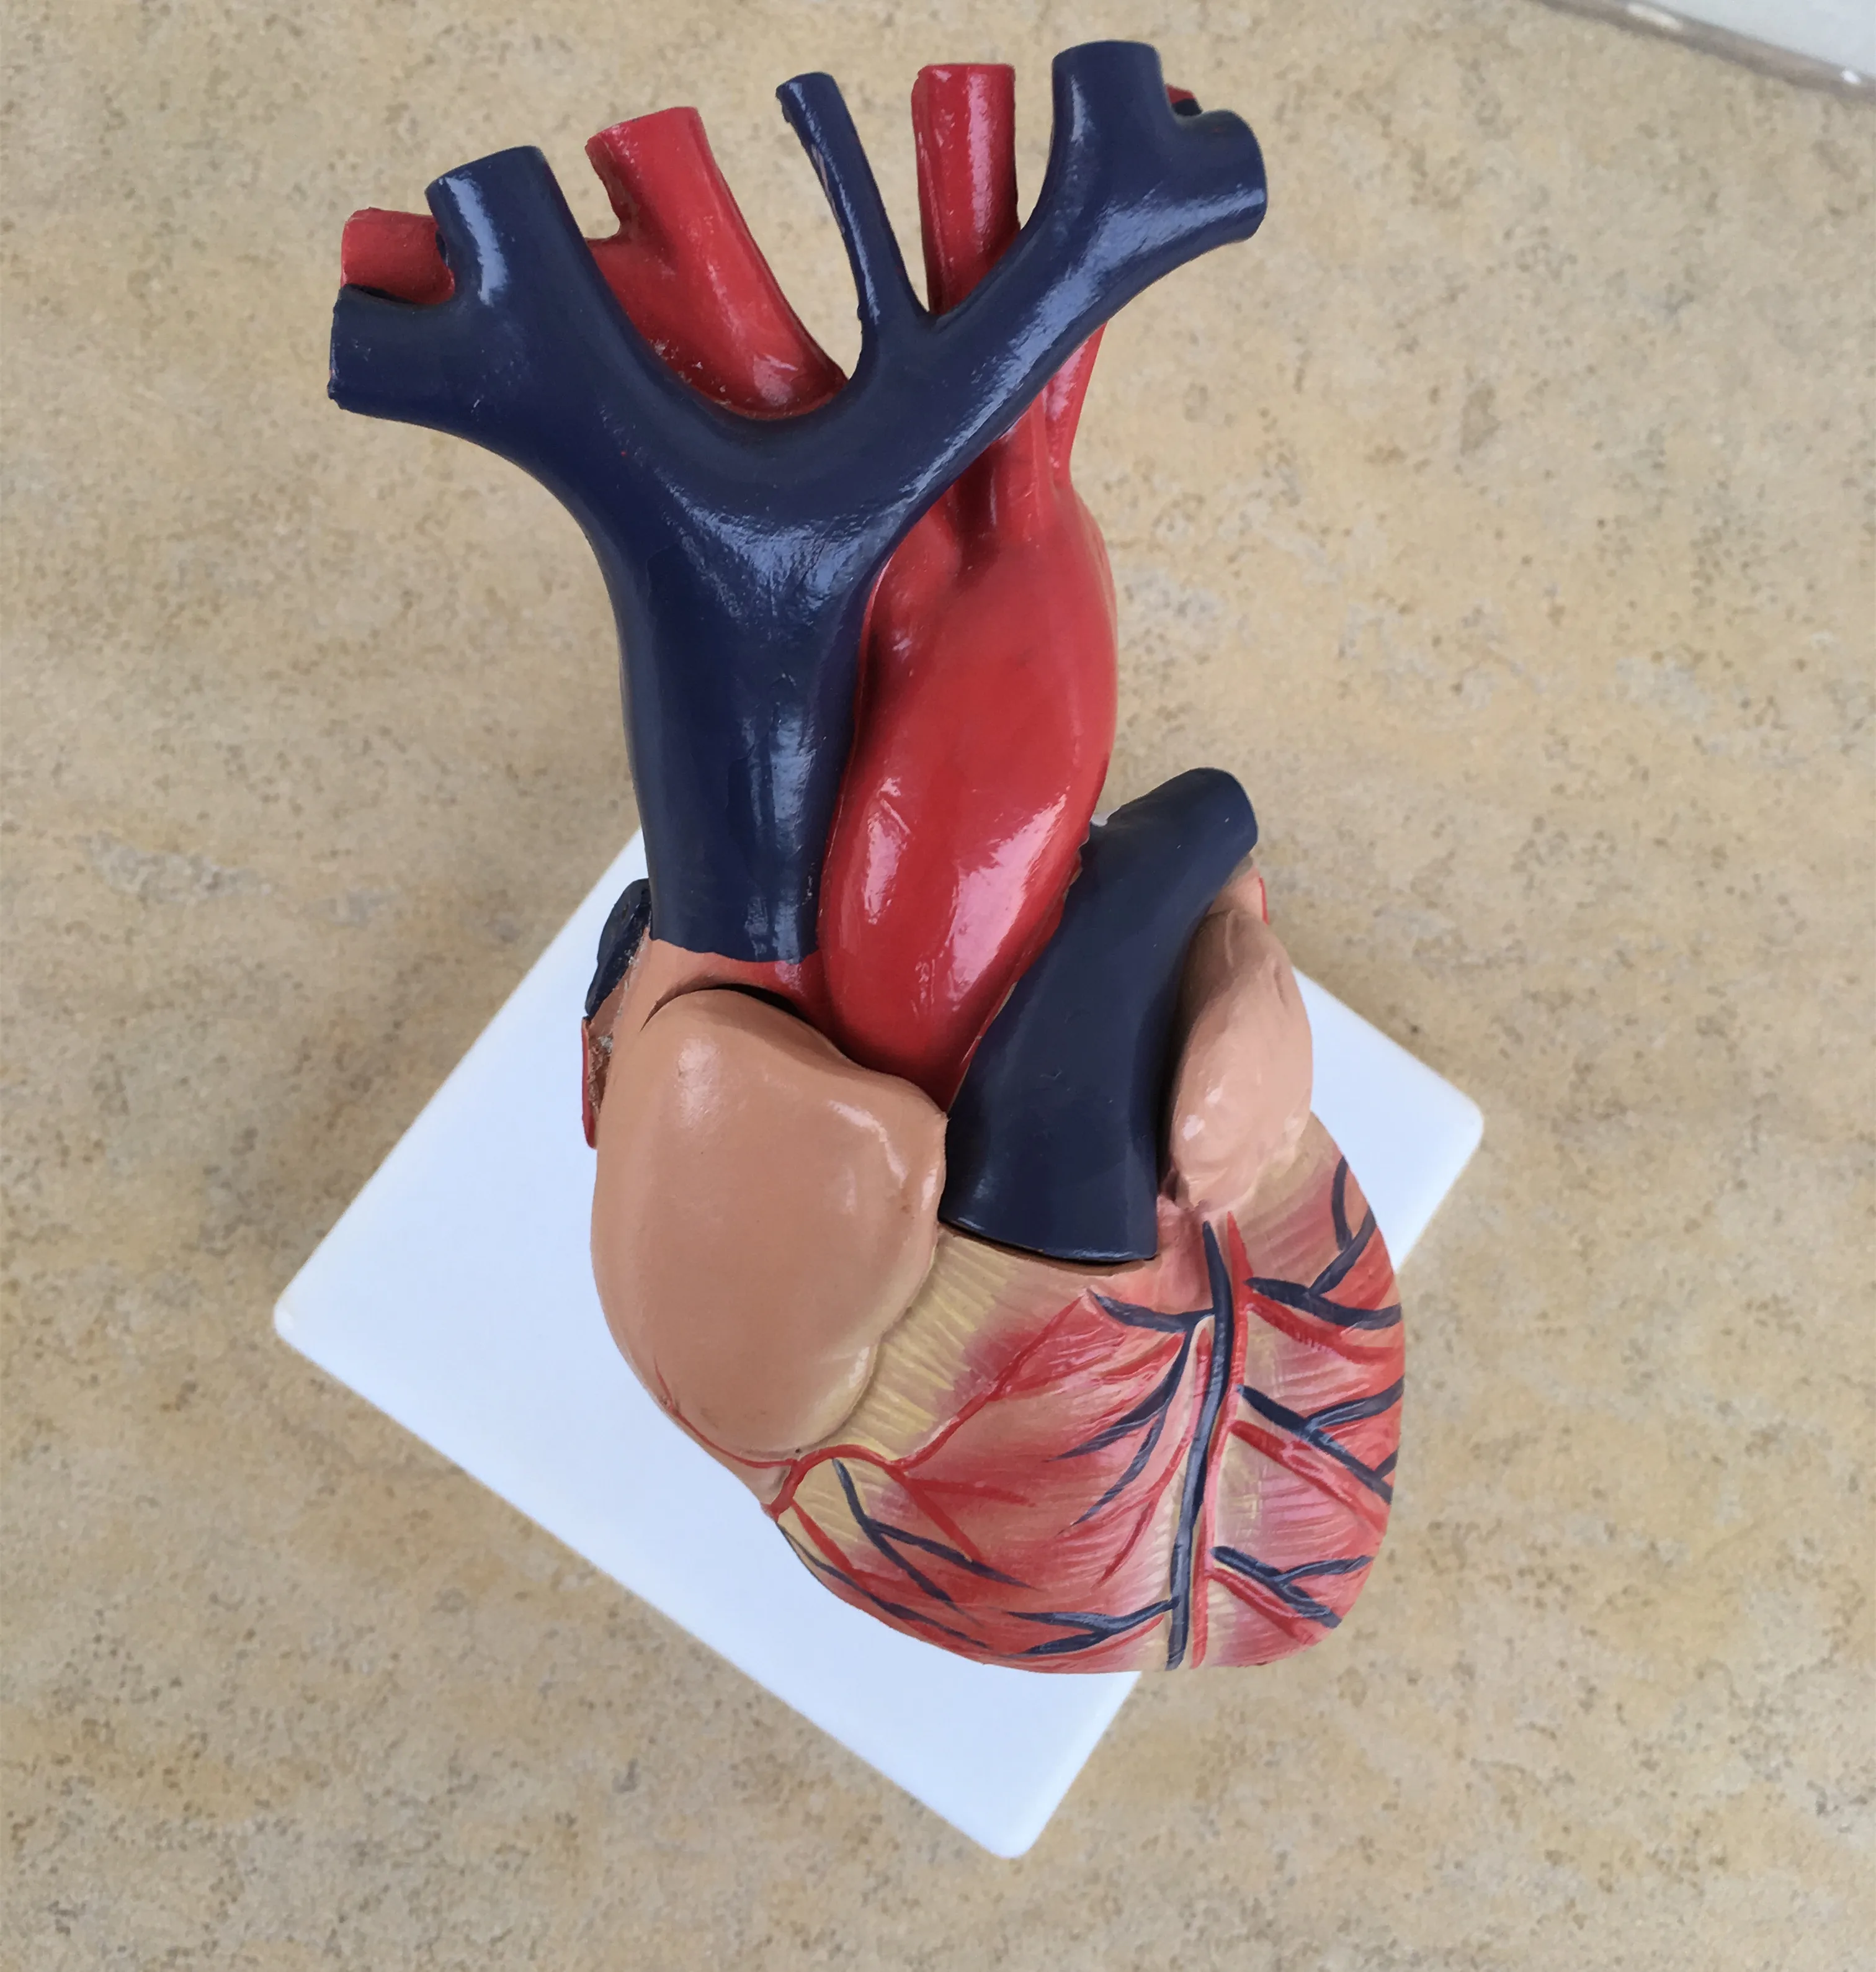

Фотографии и 3D-модели анатомии сердца человека